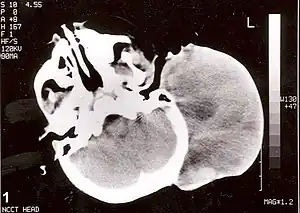

Rabdomiossarcoma (RMS) é uma variedade de sarcoma que afeta o tecido muscular esquelético, originando-se de células mesenquimais.[1]